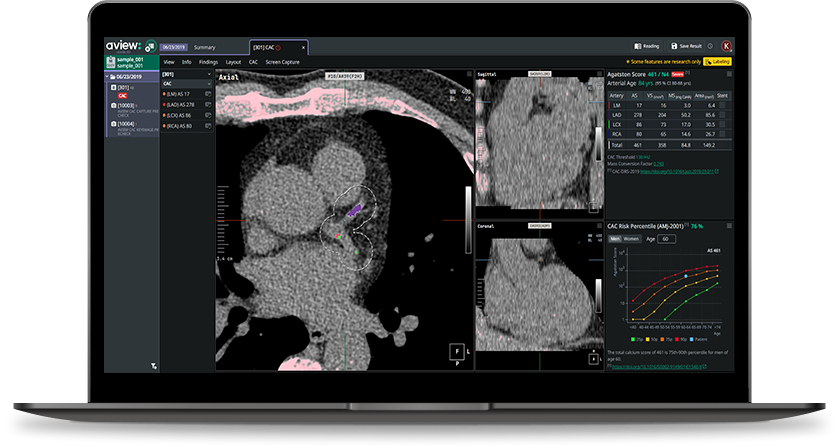

Coreline Soft's aview CAC

What an AI-Ready Workflow Looks Like: aview CAC

Coreline Soft’s aview CAC is specifically designed for this opportunistic environment:

- Kernel conversion: Automatically converts sharp kernel images (LCS standard) to soft kernel equivalents for accurate Agatston scoring.

- Anatomical segmentation: Segments the four major coronary arteries (LM, LAD, LCX, RCA) to reduce false positives from aortic or valvular calcification—a patent-protected methodology.

- Zero-click integration: Analysis runs automatically in the background. By the time a radiologist opens the viewer, results are already waiting.

- Accuracy: Agatston score agreement with ECG-gated cardiac CT reaches an ICC of 0.989.

- Prognostic Value (K-LUCAS): AVIEW CAC identified a higher CAC prevalence than visual assessment (60.1% vs. 53.4%). Patients in the "Severe" category had a 9-fold higher incidence of MACE than the "None" group (Park et al.).

- National Scale Validation: The Hagopian et al. (NEJM AI 2025) study validated AI-CAC algorithms across 98 VA centers, confirming that automated CAC detection is technically feasible and highly predictive of mortality at a national scale (Hagopian et al.).